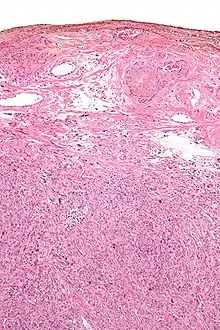

In histology, silver nitrate is used for silver staining, for demonstrating reticular fibers, proteins and nucleic acids. For this reason it is also used to demonstrate proteins in PAGE gels. It can be used as a stain in scanning electron microscopy.[14]